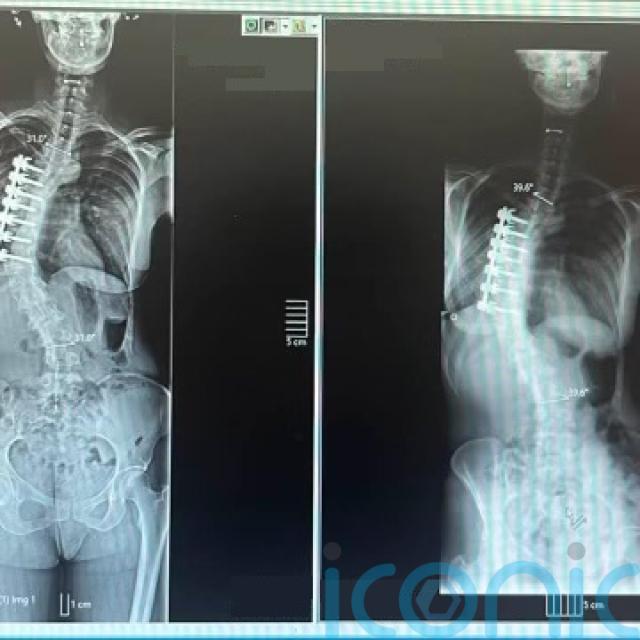

She underwent nine hours of surgery to straighten her spine, aged 12, with doctors “shaving” her right ribcage and putting a metal rod and seven bolts into her bones – but this only provided temporary relief.

With her spine continuing to collapse above and below the bolts, Laura has been left with daily pain – similar to a “constant toothache” – and said her right arm and leg are three inches longer than her left.

The body art shows the curvature in her spine, along with the rod and bolts in her bones, and she hopes to finish the design later on with flowers around it.

Back in the UK, this led to the discovery that her thoracic – the middle section of her spine – had collapsed, leading to a nine-hour operation at the John Radcliffe Hospital, Oxford, to “straighten” her back, aged 12.